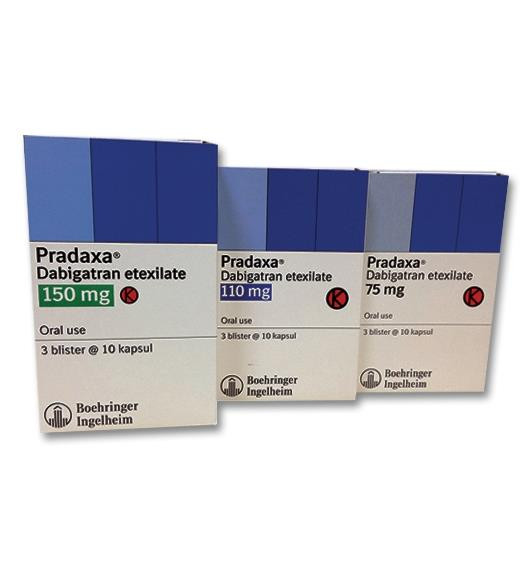

Pengobatan embolisme paru bertujuan untuk mencegah bekuan darah bertambah besar dan mencegah terbentuknya bekuan darah baru. Pengobatan yang cepat dan tepat sangat penting untuk mencegah kematian dan komplikasi lanjutan.

Obat-obatan yang digunakan antara lain:

- Pengencer darah (antikoagulan). Obat ini bertujuan untuk mencegah terbentuknya bekuan darah. Obat yang digunakan antara lain adalah heparin atau warfarin. Obat-obatan ini dapat menyebabkan perdarahan sehingga perlu digunakan dengan pengawasan ketat.

- Pemecah bekuan darah (trombolitik). Walaupun bekuan darah dapat diurai dengan sendirinya, pada beberapa kondisi, trombolitik perlu diberikan untuk mempercepat proses tersebut.

- Antikoagulan. Obat-obatan ini sering diberikan kepada orang-orang yang akan menjalani operasi, terutama mereka dengan faktor risiko tertentu (kanker, serangan jantung, atau stroke).